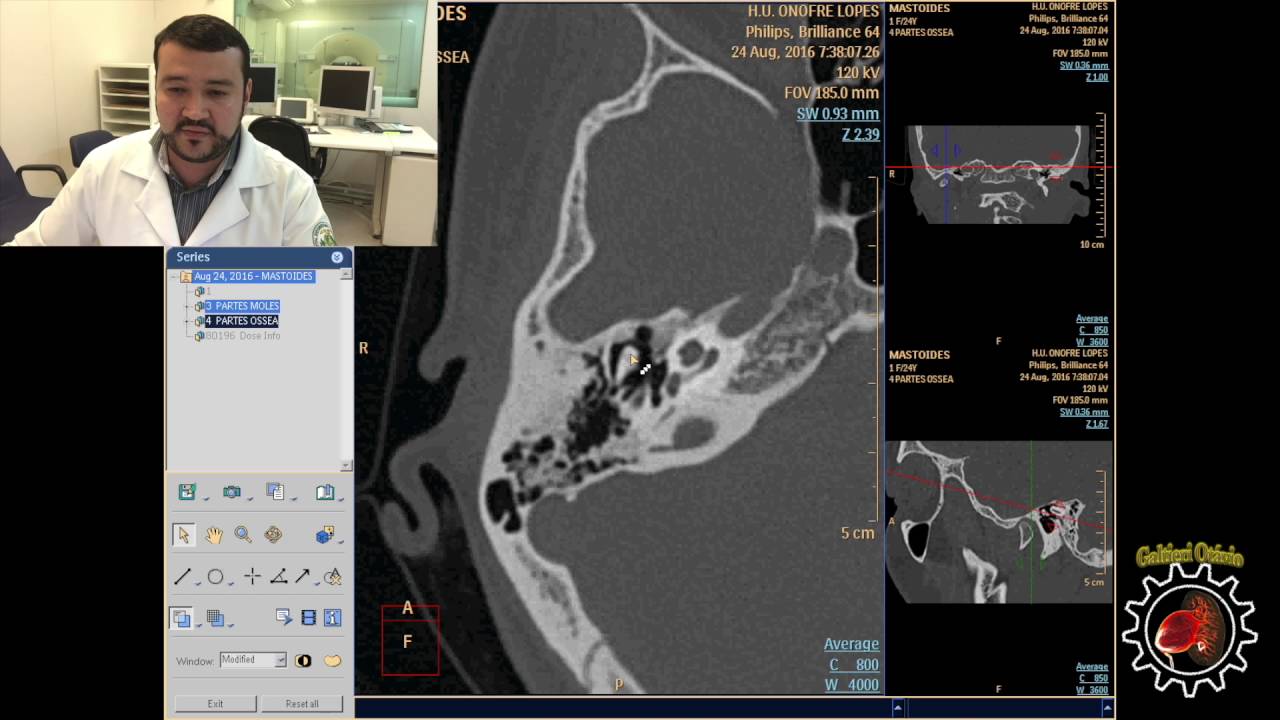

ter uma preparação especial aí para você poder fazer os procedimentos não só você como até mesmo o equipamento que você vai utilizar dentro do centro cirúrgico é um equipamento que ele está todo coberto ali com Campo cirúrgico até mesmo esse aparelho não vem a contaminar o ambiente ali e trazer uma infecção pro paciente que está em cirurgia a atuação do profissional em radiologia dentro do centro cirúrgico Pode ser na radiologia intervencionista ou cirurgias ortopédicas na radiologia intervencionista o técnico vai auxiliar ali também diretamente o médico o qu fornecendo as imagens tanto na radiologia intervencionista como

na cirurgia ortopédica o técnico ou o tecnólogo quem está operando ali o aparelho ele vai ser os olhos do médico né literalmente ele vai ser os olhos do médico porque o médico vai estar fazendo procedimento cirúrgico e ele vai estar vendo ele vai estar enxergando a cirurgia segundo o que você está passando para ele segundo a imagem que você está fornecendo para ele por isso que é importante um bom posicionamento do aparelho é importante mostrar imagens Claras porque imagem em tempo real né O médico vai estar operando ele vai estar olhando pelo monitor ele vai

estar olhando Ali pela imagem que você está fornecendo para ele então você está sendo os olhos do médico por aí você vê que é muito importante a atuação do profissional da radiologia dentro do centro cirúrgico você tá sendo os olhos do médico você está mostrando para ele o que ele está fazendo né ele está sendo guiado Pelas imagens que você está fornecendo para ele então o seu bom trabalho dentro do centro cirúrgico compromete diretamente também com o resultado dessa cirurgia com o sucesso ou não dessa cirurgia então só para entender um pouquinho sobre a Radiologia

o que o médico faz dentro do centro cirúrgico muitas vezes depende de você profissional da radiologia e existe também as cirurgias ortopédicas né muitas vezes para colocar algum pino colocar alguma prótese fios alinhamento de ossos né fraturas quando Principalmente quando é fratura exposta até mesmo fratura fechada mas uma fratura que é Cirúrgica é feito dessa maneira aí então o técnico o tecnólogo lá O estagiário ele usa aquele aparelho que é o arco inem C que nós chamamos aonde é colocado no meio o paciente fica ali na maca no meio e entrar entra aquele Arco em

C aonde é gerada essa imagem que o médico olha no monitor e consegue operar por lá né ali que ele faz os vários tipos de cirurgias tanto cirurgia Clínica como Ortopédica e a Radiologia ajuda muito o médico aí nesses tipo de cirurgia e nesse momento tanto o médico como os profissionais da enfermagem e os profissionais da radiologia devem trabalhar com uma equipe tá para que para que tudo possa acontecer da melhor maneira possível al dentro do centro cirúrgico para que tudo possa fluir e possa a cirurgia ter o sucesso esperado por isso que você estagiária